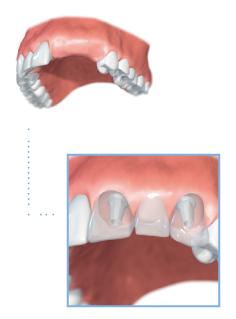

Multiple teeth

Dental implants can also be used to support multiple teeth. This usually involves the placement of two implants, which are used to support a fixed bridge.